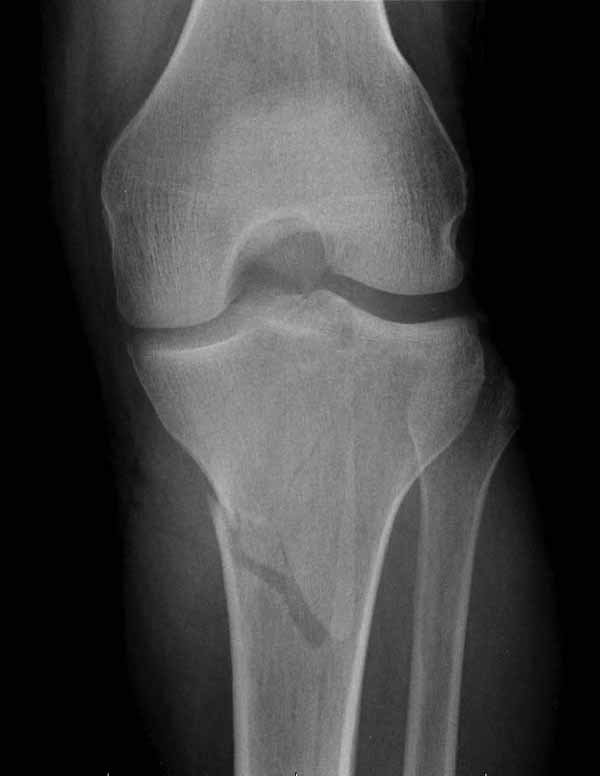

Двухколоннный перелом тибиал плато с вовлечением проксимального диафиза. Внутрисуставной компонент без смещения, и такой перелом можно лечить любым из описанных методов, о которых говорят наши коллеги.

Удобно аппаратом Илизарова или интрамедуллярным гвоздем. Гвозди не так сложно, как пугают, тем более Александр готов помощь с методичкой. Сперва надо установить компрессирующие шурупы на мыщелки. Давно отказались в пользу 3.5-4.0 мм кортикальных вместо толстых спонгиозных, потому что не доказаны преимущества толстых шурупов. Тонкие шурупы в субхондральной зоне смотрятся намного элегантнее, чем толстые 6.5.

Это мероприятие превращает перелом в простой диафизарный, который легко можно фиксировать гвоздем. Шурупы надо установить сзади предполагаемого места введения гвоздя.

Как понял, аппарат Илизарова не рассматривается предпочтительным для фиксации методом, хотя на фоне отека было бы идеальным для данного перелома. Для пластины требуется идеальная кожа, иначе наличие “суперсовременных имплантов” не поможет, и могут развиться серьезные осложнения.

Частая ошибка, когда фиксацию двух колонного перелома проводят одиночной пластиной, т.е с одной стороны, и такая фиксация не удерживает, происходит вторичноое смещение. Необходимо нейтрализовать второй пластиной или дополнительным наружным фиксатором.

Кстати, коллеги правы для уточнения характера перелома надо делать Компьютерную Томографию.

В приложении этапы фиксации Both Column Fx и пластиной Synthes для плеча при переломе медиального мыщелка.